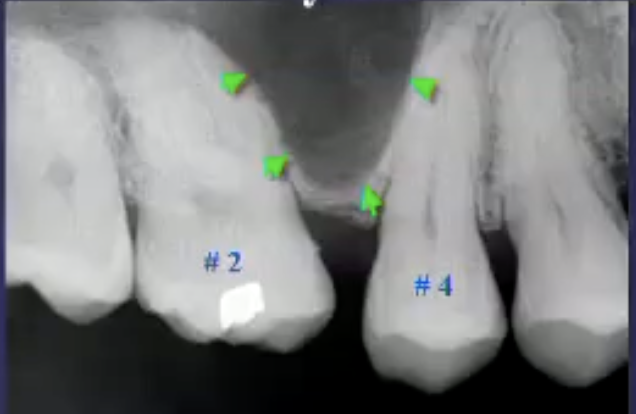

differentiate the pathology for #30 + #31

#30: apical rarefying osteitis

#31: developing tooth w/ open root apex

describe the pathology

apical sclerosing osteitis + radiolucency around PDL space